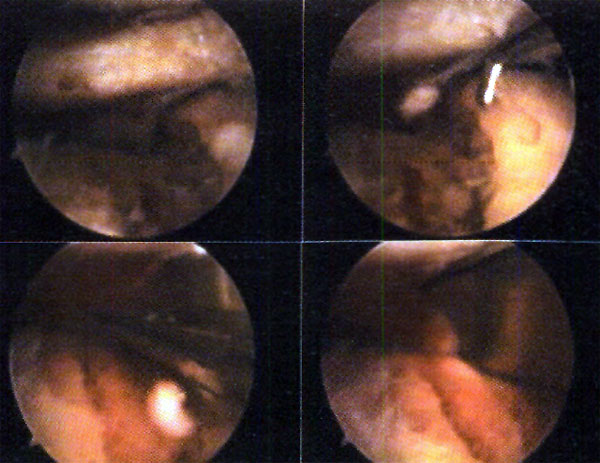

Finalizada la reducción, procedemos a rellenar el defecto óseo existente en la meseta tibial con injerto óseo obtenido de la cresta ilíaca del paciente, introduciéndolo a través de la ventana ósea efectuada en la tibia. Al mismo tiempo que impactamos el injerto controlamos bajo control artroscópico que los fragmentos de la fractura no se desplacen, o que no migre injerto óseo en la articulación. (Foto 6)

En el caso de las fracturas por cizallamiento, realizamos un abordaje longitudinal sobre el platillo afectado (evitando la apertura de la cápsula articular y la desinserción meniscal), a través del cual desimpactamos y elevamos los fragmentos cizallados. Simultáneamente y mediante un escoplo laminar o escoplo gubia, desimpactamos los fragmentos fracturarios articulares bajo visión artroscópica, colaborando en las maniobras de reducción. (Foto 7) Posteriormente realizamos la osteosíntesis, la cual dependerá de las características de la fractura que estemos tratando. Si utilizamos tomillos canulados con arandela, la colocación es percutánea próxima a la línea articular, para que actúen de sostén, protegiendo el hundimiento de los fragmentos (fracturas tipo III), o realicen compresión del fragmento cizallado (algunas fracturas tipo I y II.) La placa con tornillos es utilizada en aquellas fracturas con componente de cizallamiento, con importante conminución, desplazamiento u osteopenia de sus fragmentos.

Foto 6: Injerto compactado

Foto 7: Reducción con escoplo